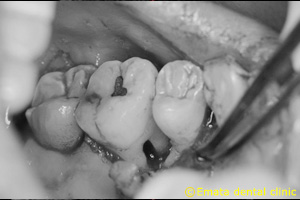

42歳 男性 主訴 奥歯が腫れて咬むと痛い

CT画像です。内側から分岐部まで破壊されいます。外側の骨は破壊されていません。

エルビウムヤグレーザーを使いエムドゲインによる再生療法をしました。

治療後のエックス線像、骨が再生されました。